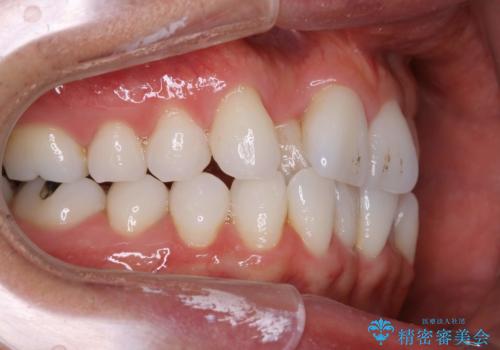

内側に入ってしまった前歯を正しい位置へ インビザライン矯正

右上の前から2番目の歯が引っ込んで、下の前歯にはガタガタがありました。

上下の歯と歯の間を少量ずつ削りスペースを作り、インビザラインにて並べる計画としました。

目立たずに矯正治療を終えることができたことに満足していただけました。